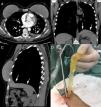

We would like to report another infrequent thoracic complication of breast prosthesis rupture: pleural silicone collection. A 51-year-old woman was admitted with abdominal pain caused by cholelithiasis. A preoperative chest X-ray showed a left pleural effusion. She was asymptomatic from a respiratory point of view. Thoracocentesis was performed, but was unsuccessful. Chest computed tomography demonstrated an elongated opacity at the base of the left hemithorax, just above the diaphragm, in the pleural cavity (Fig. 1A–C).

We therefore elected to perform a left videotoracoscopy. Exploration of the chest cavity revealed a large collection of free silicone gel in the pleural space. The silicone was evacuated manually and with suction (Fig. 1D). Clinically, the patient had an uneventful postoperative course. After 1 year, she remains asymptomatic.